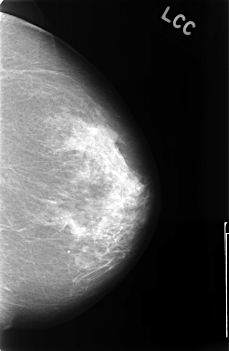

C_0420_1.LEFT_CC

LEFT_CC LINES 4552 PIXELS_PER_LINE 2976 BITS_PER_PIXEL 12 RESOLUTION 50 NON_OVERLAY